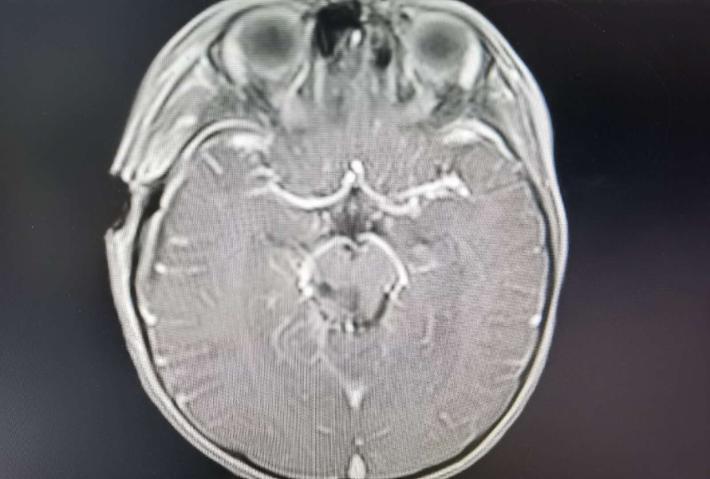

术后轴位,肿瘤消失

术后轴位,肿瘤消失,导水管通畅